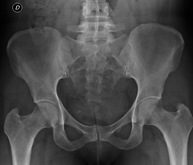

Procediment que permet, mitjançant l'ús de raigs X, i després d'injectar un contrast a l'interior de l'articulació, detectar lesions d'aquestes articulacions (cartílag, os, tendons, etc. ) segons la distribució del contrast. - RX Pelvis

Procediment que usa els raigs X a través de la qual s'obtenen imatges de la pelvis per al seu estudi, especialment dels ossos pèlvics. - RX Edat òssia

Estudi que mitjançant una radiografia de la mà permet valorar, en funció del desenvolupament dels ossos, l'edat del pacient i determinar si existeix un retard o un creixement superior pel que correspon a la seva edat. - RX Malucs pediatria

Estudi que usa els raigs X a través de la qual s'obtenen imatges del maluc i permet descartar luxacions. - RX Seriada òssia